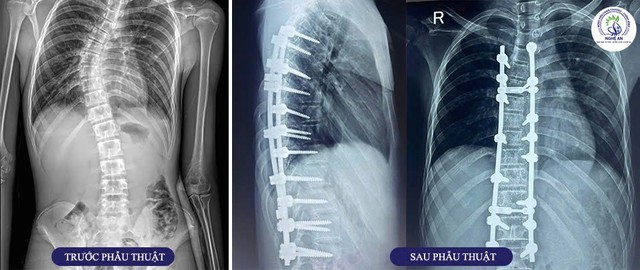

Không chỉ điều trị hiệu quả cho bệnh nhân thiếu niên và người cao tuổi, Bệnh viện Chấn thương Chỉnh hình Nghệ An tiếp tục khẳng định năng lực chuyên môn với ca phẫu thuật chỉnh hình cột sống phức tạp cho bệnh nhi nam 16 tuổi, quê ở Tân Kỳ – Nghệ An, được chẩn đoán vẹo cột sống thắt lưng do dị tật bẩm sinh đốt sống L3.

Bệnh nhân nhập viện trong tình trạng đau lưng kéo dài, biến dạng cột sống rõ rệt, ảnh hưởng đến thể lực và tâm lý. Kết quả cận lâm sàng cho thấy đường cong cột sống bị vẹo sang phải với góc Cobb 25 độ, hẹp khe đĩa đệm L2/L3, dị tật nửa thân đốt sống L3 bên phải, gù vùng cột sống thắt lưng (độ ưỡn thắt lưng – LL: 10 độ).

Sau nhiều lần hội chẩn chuyên môn, BSCKII Nguyễn Hoàng Dương – Trưởng khoa Phẫu thuật Thần kinh – Sọ não – Cột sống đã chỉ định can thiệp ngoại khoa bằng kỹ thuật bắt vít qua cuống kết hợp cắt bỏ dị tật đốt sống L3 qua đường sau.

Ca phẫu thuật diễn ra thuận lợi, hình dạng cột sống được nắn chỉnh, bệnh nhân không gặp biến chứng trong và sau mổ. Ba ngày sau phẫu thuật, bệnh nhân tỉnh táo, giảm đau, không có dấu hiệu liệt khu trú, vết mổ khô và có thể tập ngồi dậy, đi lại với sự hỗ trợ của nhân viên y tế.